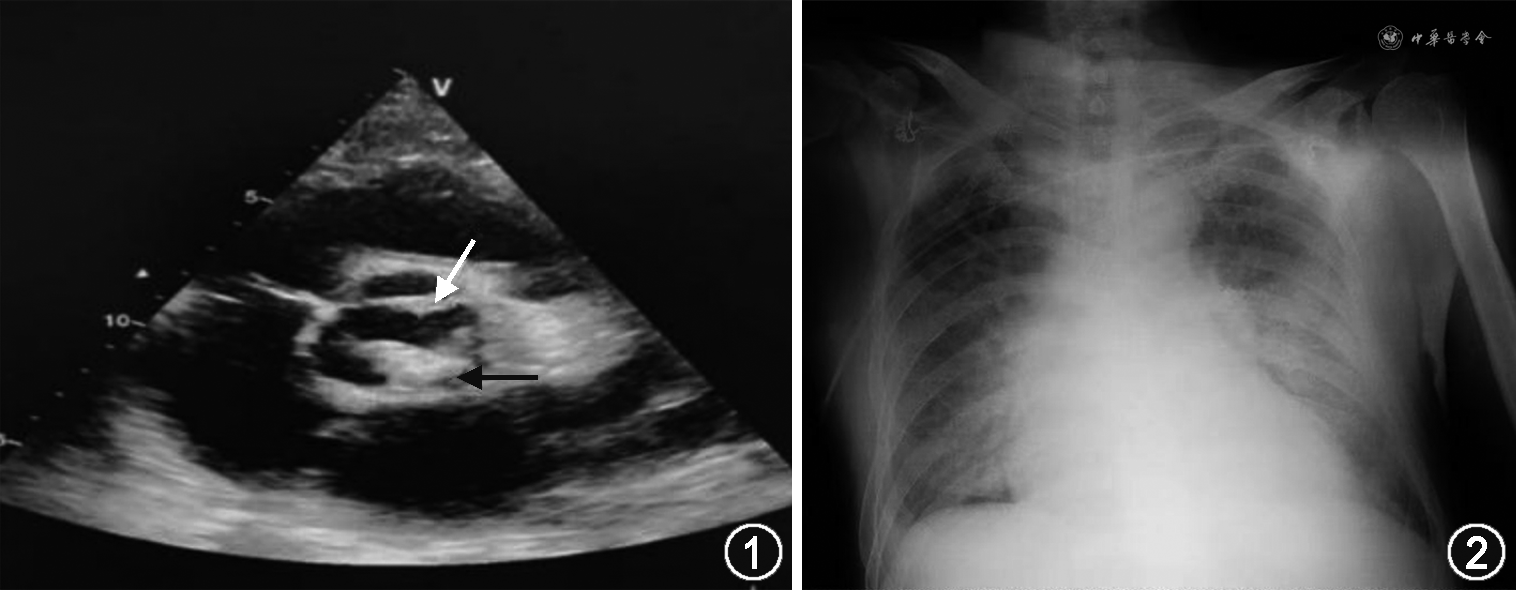

患者男,53岁,主因发热伴关节痛、睾丸痛半年余、喘憋半个月,于2020年1月收入北京协和医院感染内科病房。半年前患者在制作羊肉串时扎破手指出血,5个月前出现发热,体温最高40 ℃,伴双腕、髋关节、腰部和睾丸疼痛就诊北京协和医院门诊,查布鲁菌血清凝集试验阳性,诊断布鲁菌病,予米诺环素100 mg、利福平300 mg,每天2次抗感染治疗,患者服药次日体温即下降至正常,关节及睾丸疼痛逐渐减轻,规律服用上述药物治疗3个月,期间无下肢浮肿、喘憋等不适症状,未行心脏彩超检查。半个月前患者无明显诱因出现活动后气短、喘憋,夜间不能平卧,端坐呼吸,咯血色泡沫样痰,无发热、少尿等,就诊于北京某医院,行心脏彩超提示主动脉瓣关闭不全(重度),肺动脉高压,气管镜检查未见异常,予青霉素抗感染、止血等治疗后喘憋无明显好转,后出现双下肢浮肿,活动耐量下降,平地走100米左右即出现气促喘憋,再次就诊北京协和医院,急诊查心脏彩超提示主动脉瓣轻度狭窄伴重度关闭不全,主动脉瓣赘生物可能(图1),为进一步治疗入院。既往高血压病史20余年,慢性肾功能不全史9年。入院体检:体温38 ℃,脉搏90次/min,呼吸21次/min,血压110/60 mmHg(1 mmHg=0.133 kPa),肝颈静脉回流征阴性,双肺未及干湿啰音,心界无扩大,心率90次/min,律齐,主动脉瓣第二听诊区可闻及舒张期吹风样杂音,余瓣膜听诊区未及杂音,可扪及水冲脉,周围血管征阳性,双下肢轻度可凹性浮肿。

入院后查血常规:白细胞6.47×109/L,中性粒细胞百分比78.8%,血红蛋白109 g/L,血小板计数186×109/L。肝肾功能:丙氨酸转氨酶(ALT)17 U/L,肌酐(Cr)94 μmol/L,白蛋白33 g/L,K 3.9 mmol/L;NT-proBNP 9 074 ng/L,cTnI 0.055 μg/L,CK 155 U/L。胸部CT示双侧胸腔积液。予利尿、纠正电解质失衡等对症治疗,患者诉喘憋较前改善,咯少量血性痰,夜间可间断平卧入睡,间断发热,最高体温38.1 ℃。入院次日中午突然出现喘憋加重,咯大量暗红色血性痰,不能平卧,心率增快,血压下降,血氧饱和度下降,复查床旁胸片提示左心增大,呈靴型心改变,双肺门多发渗出影(图2)。给予BIPAP呼吸机辅助呼吸,心电监护、多巴胺泵入升压及利尿等处理后患者血压心率逐渐好转。外周血培养需氧瓶87小时报警提示革兰阴性球杆菌。给予左氧氟沙星0.5 g、每天1次,头孢曲松2 g、每12小时1次,米诺环素0.1 g、每天2次,抗感染治疗,患者体温逐渐下降至正常,血培养鉴定为布鲁菌,确诊布鲁菌心内膜炎,抗感染治疗后体温正常,但监测ALT、Cr逐渐升高,查体发现肝脏较前增大,肋下3 cm,入院后7 d查 Cr 299 μmol/L,血钾6.0 mmol/L,ALT 1 895 U/L;凝血 PT 22.1 s,INR 1.99,APTT 28.0 s,TT 18.3 s,因急性肝衰竭、急性肾衰竭转入重症监护病房持续CRRT脱水、纠正电解质、改善肝肾功能,稳定血流动力学。入院后第11天于“全麻低温体外循环下行开胸探查+主动脉瓣人工机械瓣置换术+三尖瓣成形术+右房壁脓肿清除术+右心房重建术”,术中见主动脉瓣赘生物,予切除后送检,右心房壁可见大量脓液。术后组织病理回报:主动脉瓣退变的瓣膜组织,伴玻璃样变性及钙化,可见较多退变坏死物。组织培养(-)。患者术后次日间断出现房颤,胺碘酮治疗后仍未复律,给予120J电复律2次后恢复窦律,脱机拔管,继续头孢曲松2 g、12小时1次,米诺环素100 mg、12小时1次,抗感染治疗,疗程6周。患者体温及各项感染指标稳定,住院46 d后病情好转出院。出院1个月余随访出现腰椎关节不适,因其口服米诺环素及利福平胃肠道反应明显,回当地医院继续随诊。6个月后于北京佑安医院查血培养布鲁菌阳性,持续“蒙药”治疗中,患者一般状况良好。